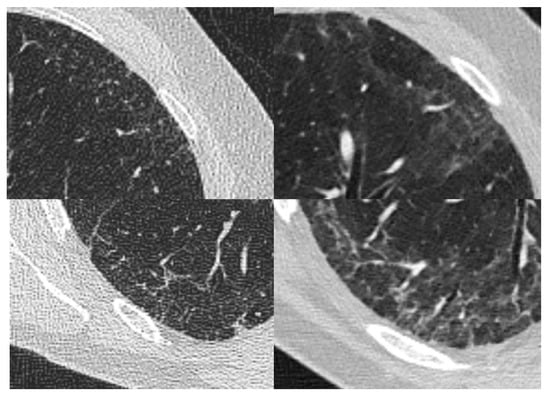

2. Case Report